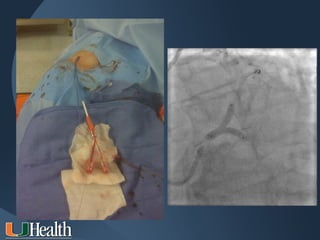

Right Heart Catheterization

via Antecubital Vein